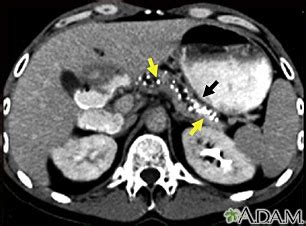

- Tomografía Computarizada (TC) Abdominal: Ofrece imágenes detalladas del páncreas, mostrando cambios de la pancreatitis crónica y detectando posibles complicaciones como seudoquistes.

- Seudoquistes Pancreáticos: Acumulaciones de líquido y residuos que pueden causar dolor, sangrar, romperse o bloquear el duodeno o las vías biliares.